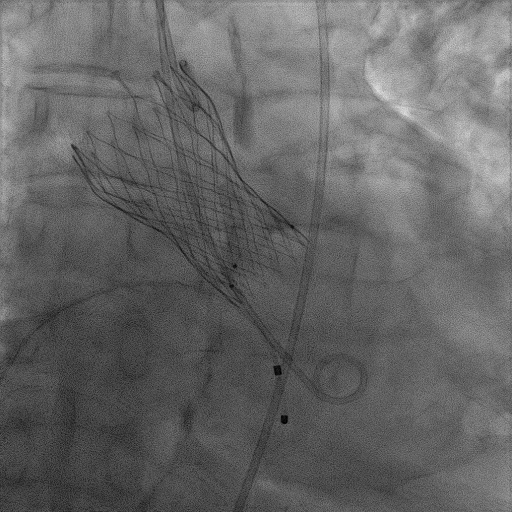

患者麻醉方式为全麻,建立静脉通路后,穿刺右侧股静脉,预埋ProGlide缝合器,食道超声指导下房间隔穿刺成功,将Superstiff导丝送至左房,应用18F鞘管扩张穿刺部位,沿导丝将导引导管送入左房,MitraClip调整后顺利到达二尖瓣目标位置,在X线及食道超声辅助下,将Mitraclip NTR成形夹精确定位后,成功夹合二尖瓣A2-P2区,超声显示反流明显减少,多切面证实夹合组织充分,肺静脉多普勒波形由反向恢复正常,手术顺利结束,安返普通病房。

3D视图打开夹子

X-plane:下第夹子尝试捕获2区

X-plane:测量前叶长25mm,后叶长14.2mm

X-plane:计算前叶捕获长度8mm,后叶捕获长度7mm

3D视图下观察二尖瓣双孔形态

3D-color:残余少量返流